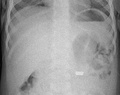

A coin seen on AP CXR in the esophagus

AP X ray showing a 9mm battery in the intestines